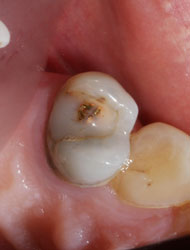

Такая же негерметичная пломба, такой же анкерный штифт… при этом твердые ткани сохранены гораздо лучше первого случая. По всему периметру зуба граница полости находится выше уровня десны, а, значит, по крайней мере, прогноз на долговечность реставрации будет вполне оптимистичным.

После удаления старой пломбы и анкерного штифта можно увидеть, что происходит внутри зуба под внешне вроде бы неплохой пломбой.